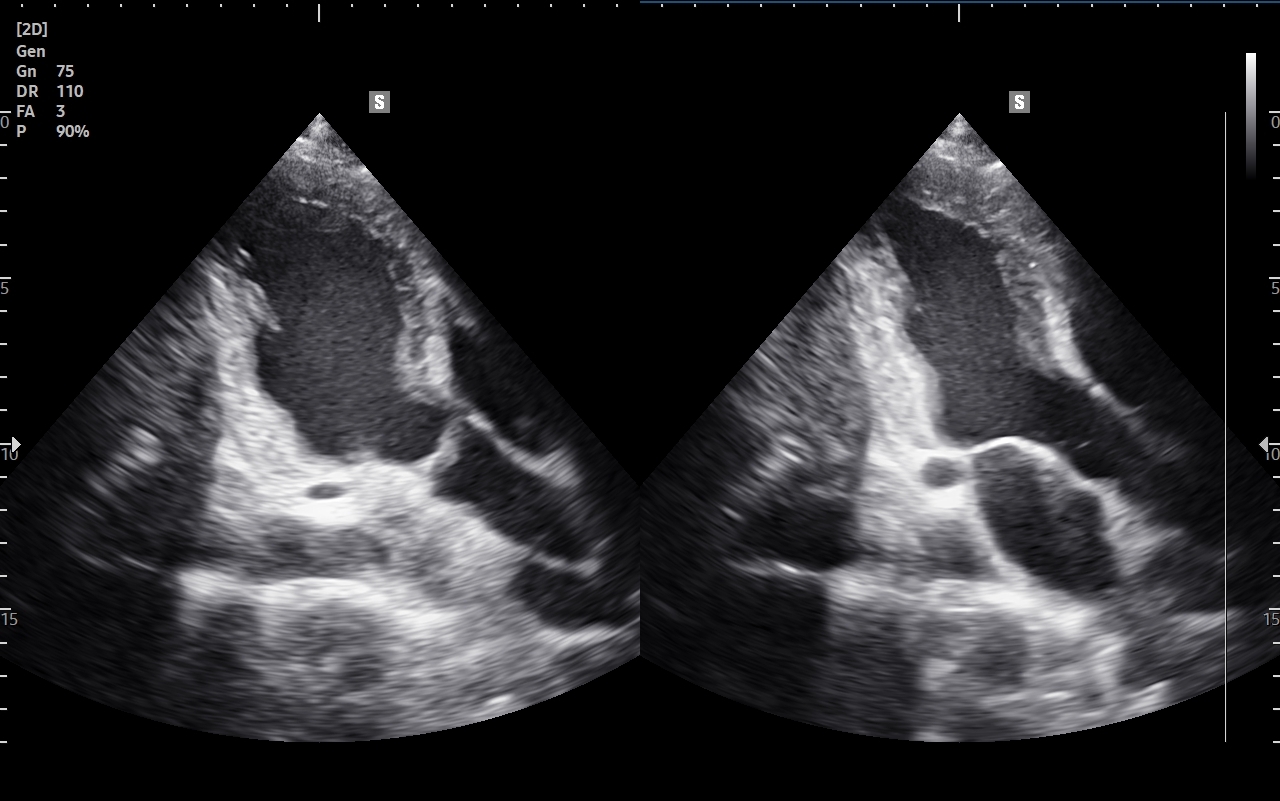

Badanie USG Doppler tętnic wewnątrzczaszkowych (ang. TCCD, transcranial color-coded Doppler), nazywane także Dopplerem przezczaszkowym jest naturalnym rozszerzeniem i uzupełnieniem badania dopplerowskiego tętnic dogłowowych zewnątrzczaszkowych. Badanie polega na obrazowaniu przy użyciu dedykowanej sondy poprzez tzw. okno skroniowe czaszki głównych naczyń tętniczych mózgu, tj. koła Willisa, tętnic mózgowych przednich, środkowych i tylnych po obu stronach. Badanie TCCD umożliwia wykrycie wybranych wewnątrzczaszkowych patologii naczyniowych takich jak tętniaki, malformacje naczyniowe, zwężenia i niedrożności poszczególnych tętnic mózgowych, spazm naczyniowy, a także pozwala na ocenę kierunku przepływy krwi w kole Willisa mózgu, co  jest przydatne przy diagnostyce zespołu podkradania lub w ocenie po przebyciu udaru mózgowego.